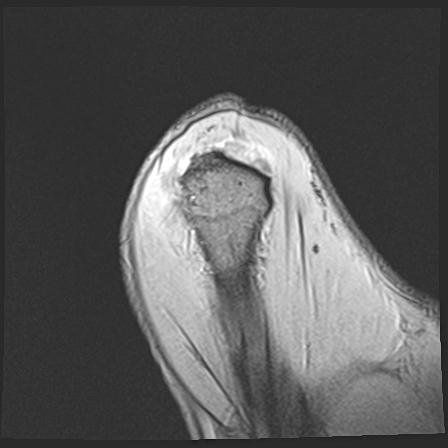

60058 3/9 11/4 右肩 2R+MRI 73歳男性 肩腱板損傷